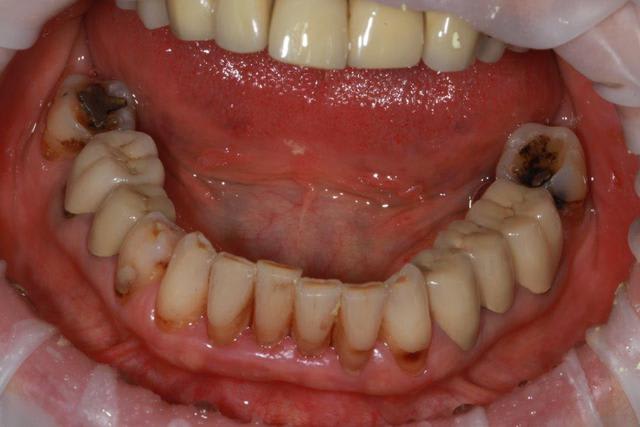

Rien qu en regardant la photo de face , je te dis oui :

L aspect de la gencives et la forme des dents suffit .

Même si les limites prophétiques étaient correctes , il y aurait ce style de gencives .

Merci enlaye pour tes réponses qui alimentent ma réflexion. Si un problème occlusal et d’ajustement des couronnes est iatrogène, les même cause conduisant les même effets pourquoi le maxillaire inférieur ne présente pas le même aspect secteur 3 ?

C'est la théorie du maillon faible (issue de mes propres constatations cliniques) : Lorsqu'il y a un problème occlusal, cela aboutit à une usure prématurée des dents lorsque les racines sont longues et le parodonte solide ; dans le cas contraire (racine courte, frêle, parodonte peu épais...) cela aboutit à une mobilité dentaire...

Cela a permis à carident de rappeler une règle fondamentale « en cas de déséquilibre dans les forces masticatoires il est important d’identifier le maillon faible » le choix d’enlaye sur un bridge résine me semble moins traumatisant pour les racines et son support que des emax.

En plus de ce que t a dit carident, il y a une notion d anciennete . le temps passe et fait son degat

personnellement je ne vois pas de grosse différence secteur 3 et 4, mis à part "l'implant" inter-radiculaire